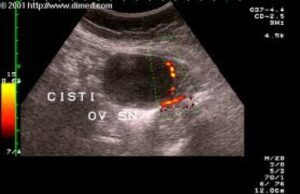

Questo può causare dolori addominali, spesso con una leggera febbre, al momento dell’ovulazione (nei giorni intermedi tra le mestruazioni). Il trattamento potrebbe consistere solo nella somministrazione di un antidolorifico come ibuprofene, rassicurazione della paziente, riposo e se necessario un impacco caldo. Più tardi nella vita, di solito dopo i 35 anni, le donne possono sviluppare una cisti ovarica che può non causare alcun sintomo, oppure può causare dolori pelvici che vanno da lievi a gravi. La cisti può semplicemente collassare e scomparire dopo uno o due mesi, oppure può persistere e aumentare di dimensioni creando notevole disagio durante i mesi successivi. Tali cisti sono causate da un’ovulazione fallita in cui, per motivi attualmente sconosciuti, l’ovulazione non è andata a buon fine. cicli anovulatori. Ad ogni mese successivo si assiste ad un naturale aumento di LH (ormone luteinizante) che causa un ingrandimento della cisti con estensione della membrana superficiale, causando dolore e a volte un sanguinamento. Alcune cisti possono diventare grandi come una palla da golf o un limone prima di essere scoperte. Il trattamento può richiedere un intervento chirurgico. (La rimozione dell’ovaio insieme alla cisti era la procedura standard, ma vi consiglio di chiedere al vostro chirurgo di lasciare intatta l’ovaia se possibile.) Un trattamento alternativo per le cisti ovariche è il progesterone naturale. Il meccanismo di segnalazione che interrompe l’ovulazione in un’ovaia ad ogni ciclo è la produzione di progesterone nell’altra. Se supplementiamo sufficientemente progesterone naturale prima dell’ovulazione, i livelli di LH verranno inibiti ed entrambe le ovaie “penseranno” che l’altra abbia ovulato, e quindi non si verificherà un’ovulazione regolare. (Questo è lo stesso effetto delle pillole contraccettive.) Allo stesso modo, gli elevati livelli di estriolo e progesterone durante la gravidanza inibiscono con successo l’attività ovarica per nove mesi. Pertanto, l’aggiunta di progesterone naturale dal giorno 10 al giorno 26 del ciclo sopprime l’ LH e i suoi effetti luteinizzanti. Così la cisti ovarica non sarà stimolata e, nel passaggio di uno o due cicli mensili, molto probabilmente si ridurrà e scomparirà senza ulteriori trattamenti